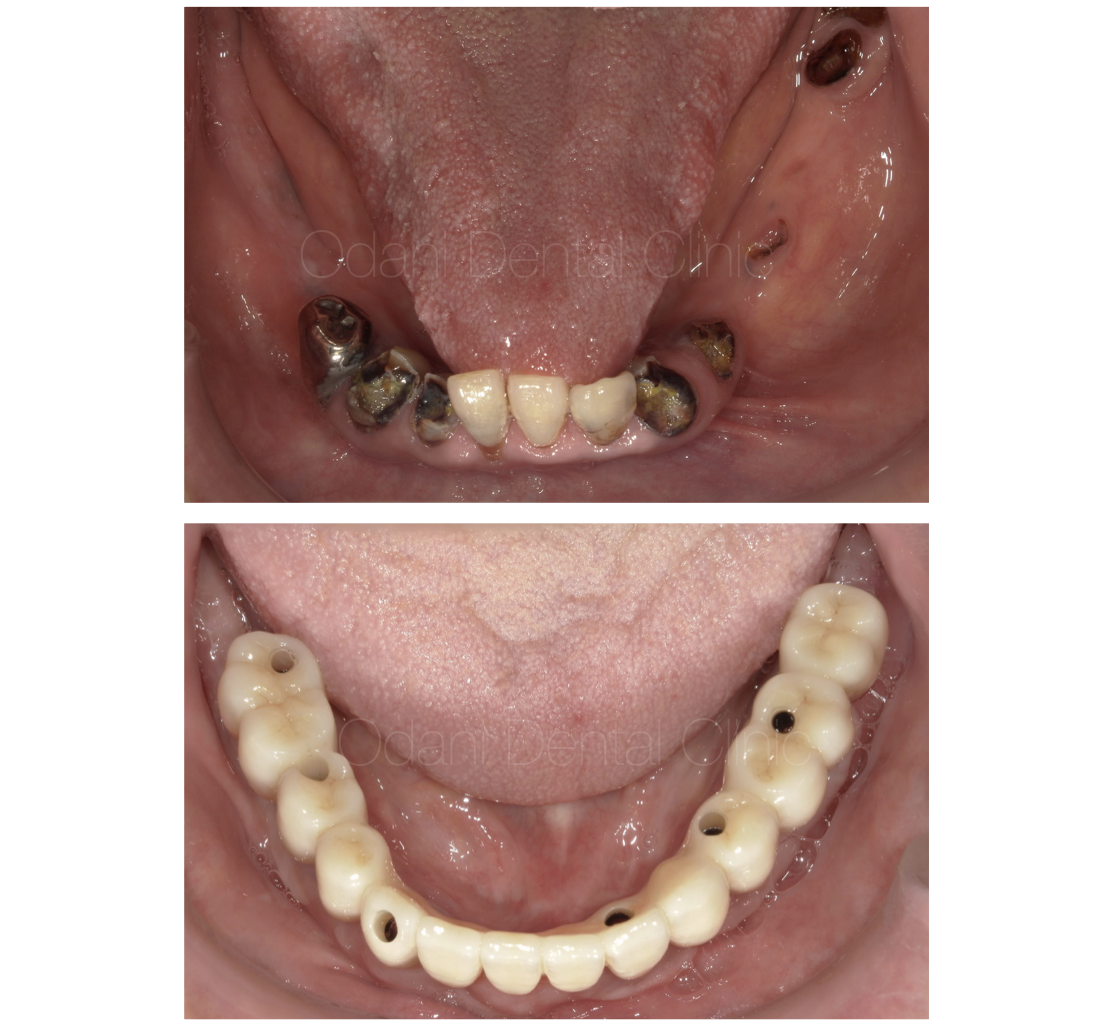

60代 男性 弱った歯の感染の影響で、抜歯後に大きな凹みを生じている症例です。

一次手術治癒後の状態です。骨造成を図ったことで、もともとの歯ぐきのヘコみが改善しました。

最終上部構造完成時です。段差があった骨のラインは整い、天然の歯とインプラントの歯、そして周囲の歯ぐきも整い、歯ブラシと1本の歯間ブラシのみで清掃が可能となりました。

術前・術後の比較